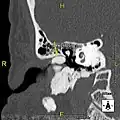

Exostoses in the ear canal, as seen through otoscopy

Surfer's ear is the common name for an exostosis or abnormal bone growth within the ear canal. They are otherwise benign hyperplasias (growths) of the tympanic bone thought to be caused by frequent cold-water exposure.[1] Cases are often asymptomatic.[1] Surfer's ear is not the same as swimmer's ear, although infection can result as a side effect.

Irritation from cold wind and water exposure causes the bone surrounding the ear canal to develop lumps of new bony growth which constrict the ear canal. Where the ear canal is actually blocked by this condition, water and wax can become trapped and give rise to infection. The condition is so named due to its high prevalence among cold water surfers, although it can occur in any water temperature due to the evaporative cooling caused by wind and the presence of water in the ear canal.

The normal ear canal is approximately 7 mm in diameter and has a volume of approximately 0.8 ml (approximately one-sixth of a teaspoon).[5] As the condition progresses, the diameter narrows and can even close completely if untreated, although people generally seek help once the passage has constricted to 0.5–2 mm due to the noticeable hearing impairment. While not necessarily harmful in and of itself, constriction of the ear canal from these growths can trap debris, leading to painful and difficult to treat infections.